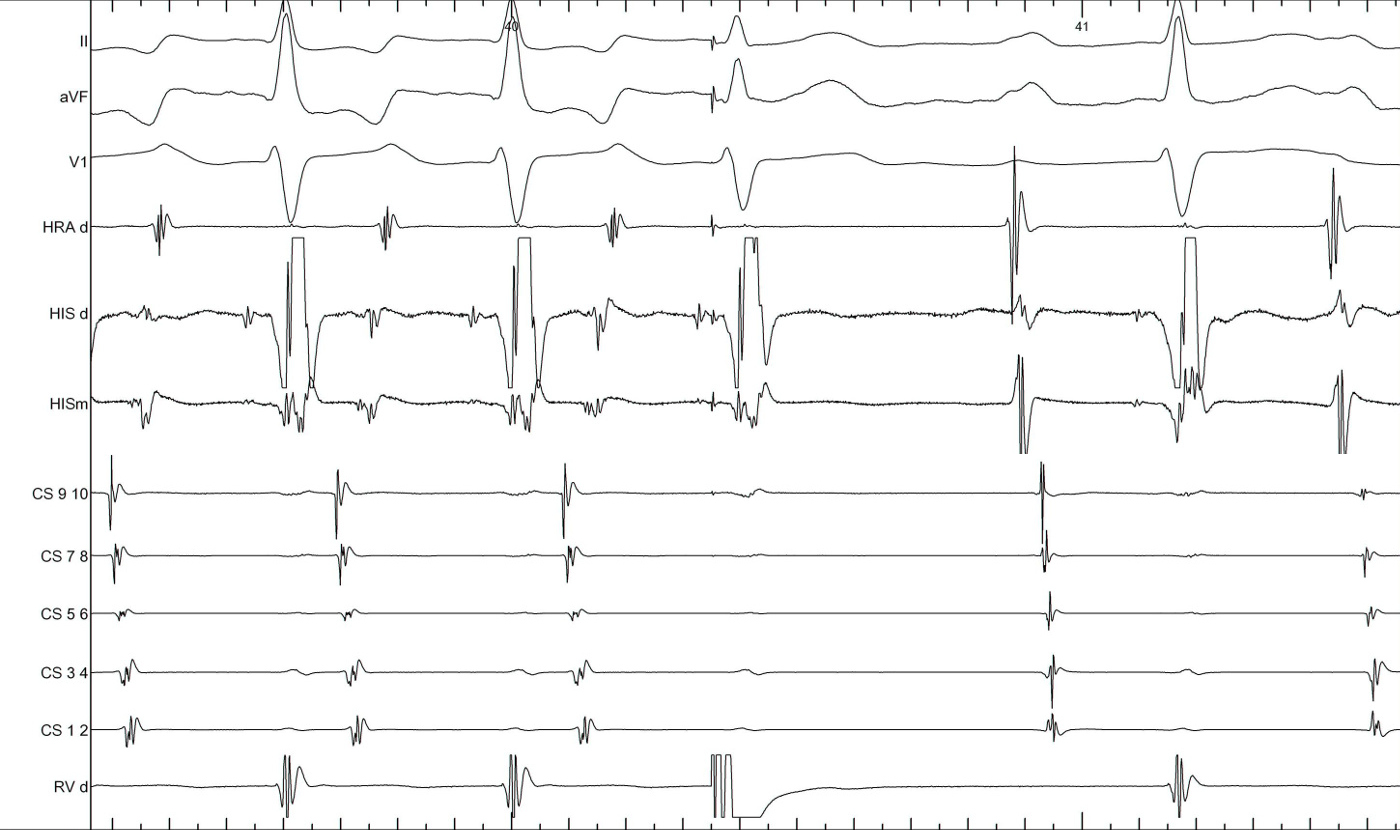

RV pacing in narrow QRS tachycardia - Rule out (or in) AT

vav.jpg

vav_measurements_atrium_entrain.jpg

RV pacing in narrow QRS tachycardia.

pseudoVAAV.png

Why all this fuss about measurement ?

pseudo_vaav_measurements.jpg

RV pacing in AT - VAAV

VAAV.jpg

RV pacing in narrow QRS tachycardia - AVNRT / AVRT

vav_measurements_ppi.jpg